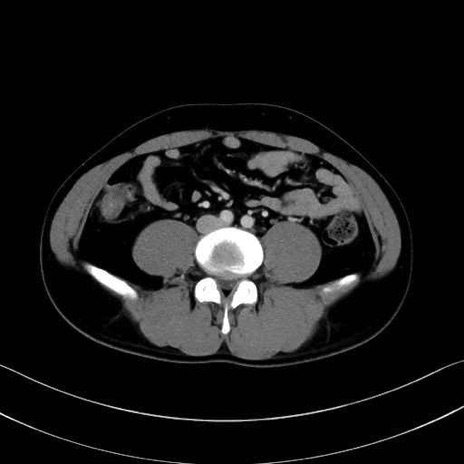

1. 体幹部(腹部・背部・後腹壁)の筋肉

腹直筋 (Rectus abdominis)

外腹斜筋 (External oblique)

内腹斜筋 (Internal oblique)

腹横筋 (Transversus abdominis)

腰方形筋 (Quadratus lumborum)